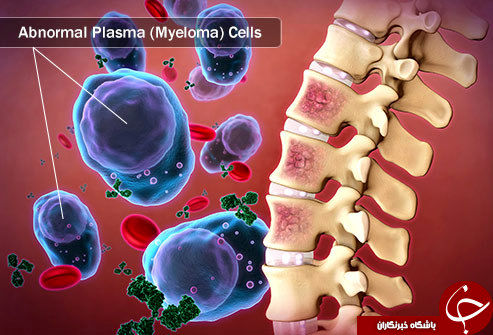

عکس سرطان استخوان. برخی از انواع اصلی سرطان استخوان عبارتند از. سرطان مغز استخوان یکی از انواع سرطان است که به دلیل اختلال در تولید گلبول ها و پلاکت های بدن به وجود می آید. رشد ناهنجار استخوان می تواند بدخیم یا خوش خیم باشد. این تصویر سرطان استخوان است که کاملا روی جمجمه قابل دیدن می باشد.

روش های عکس برداری می توانند به تعیین محل و اندازه ی تومورهای استخوان و گسترش یا عدم گسترش آن ها به سایر نقاط بدن کمک کنند. در این مقاله با علائم سرطان مغز استخوان و نیز روش های درمان آن آشنا می شوید. یک تومور رشد غیر طبیعی بافت در بدن است. سلول های توموری توانایی تنظیم کردن ندارند بنابراین سلول های بیشتری تولید می کنند و منجر به تشکیل یک توده می شوند در حالی که بسیاری از تومورها سرطانی.

تشخیص سرطان استخوان. استئوسارکوم شایع ترین نوع است که بیشتر بر کودکان و نوجوانان زیر 20 سال تأثیر می گذارد. جراحی اغلب اولین انتخاب درمانی می باشد اگرچه گاهی اوقات قطع کردن عضو لازم می باشد. درمان سرطان استخوان به نوع سرطان بستگی دارد.